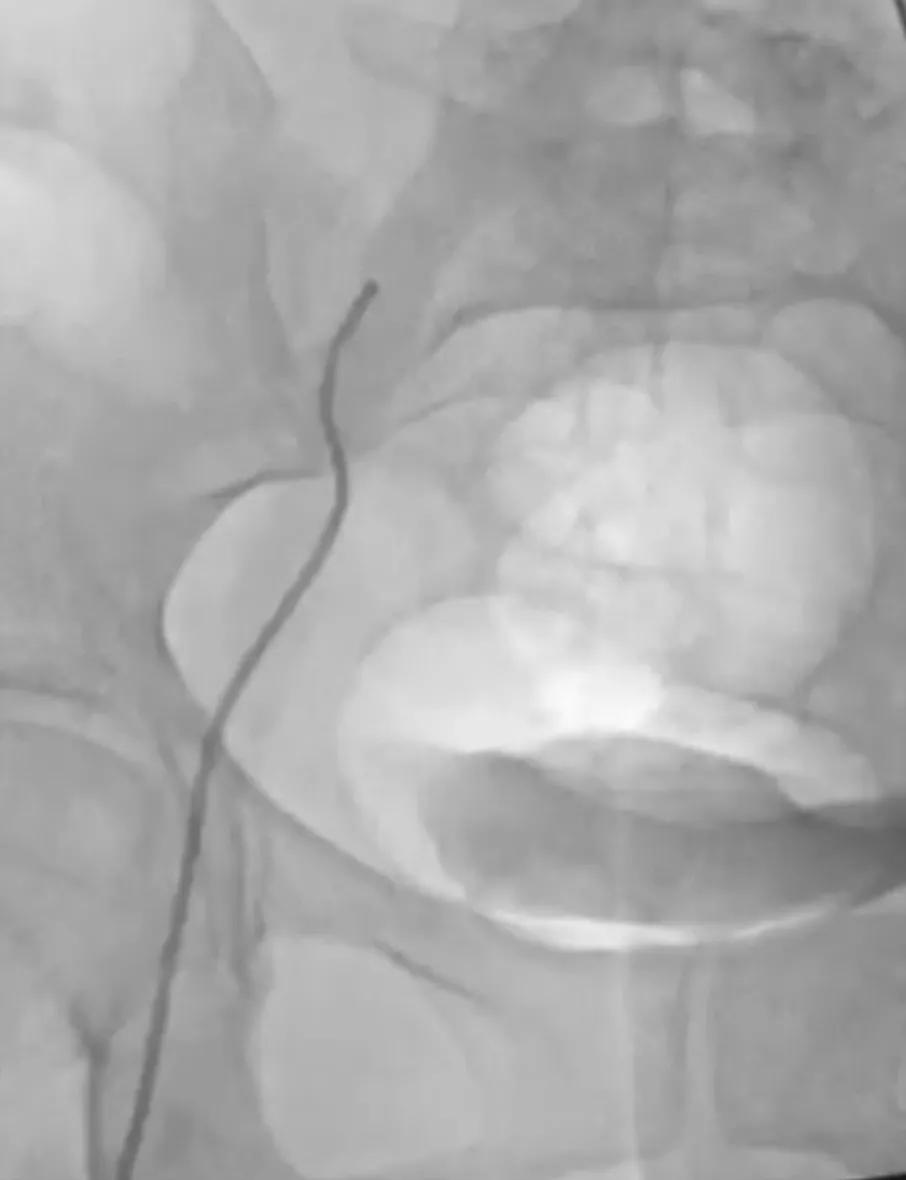

Cleaner 血栓切除装置在髂静脉处呈现